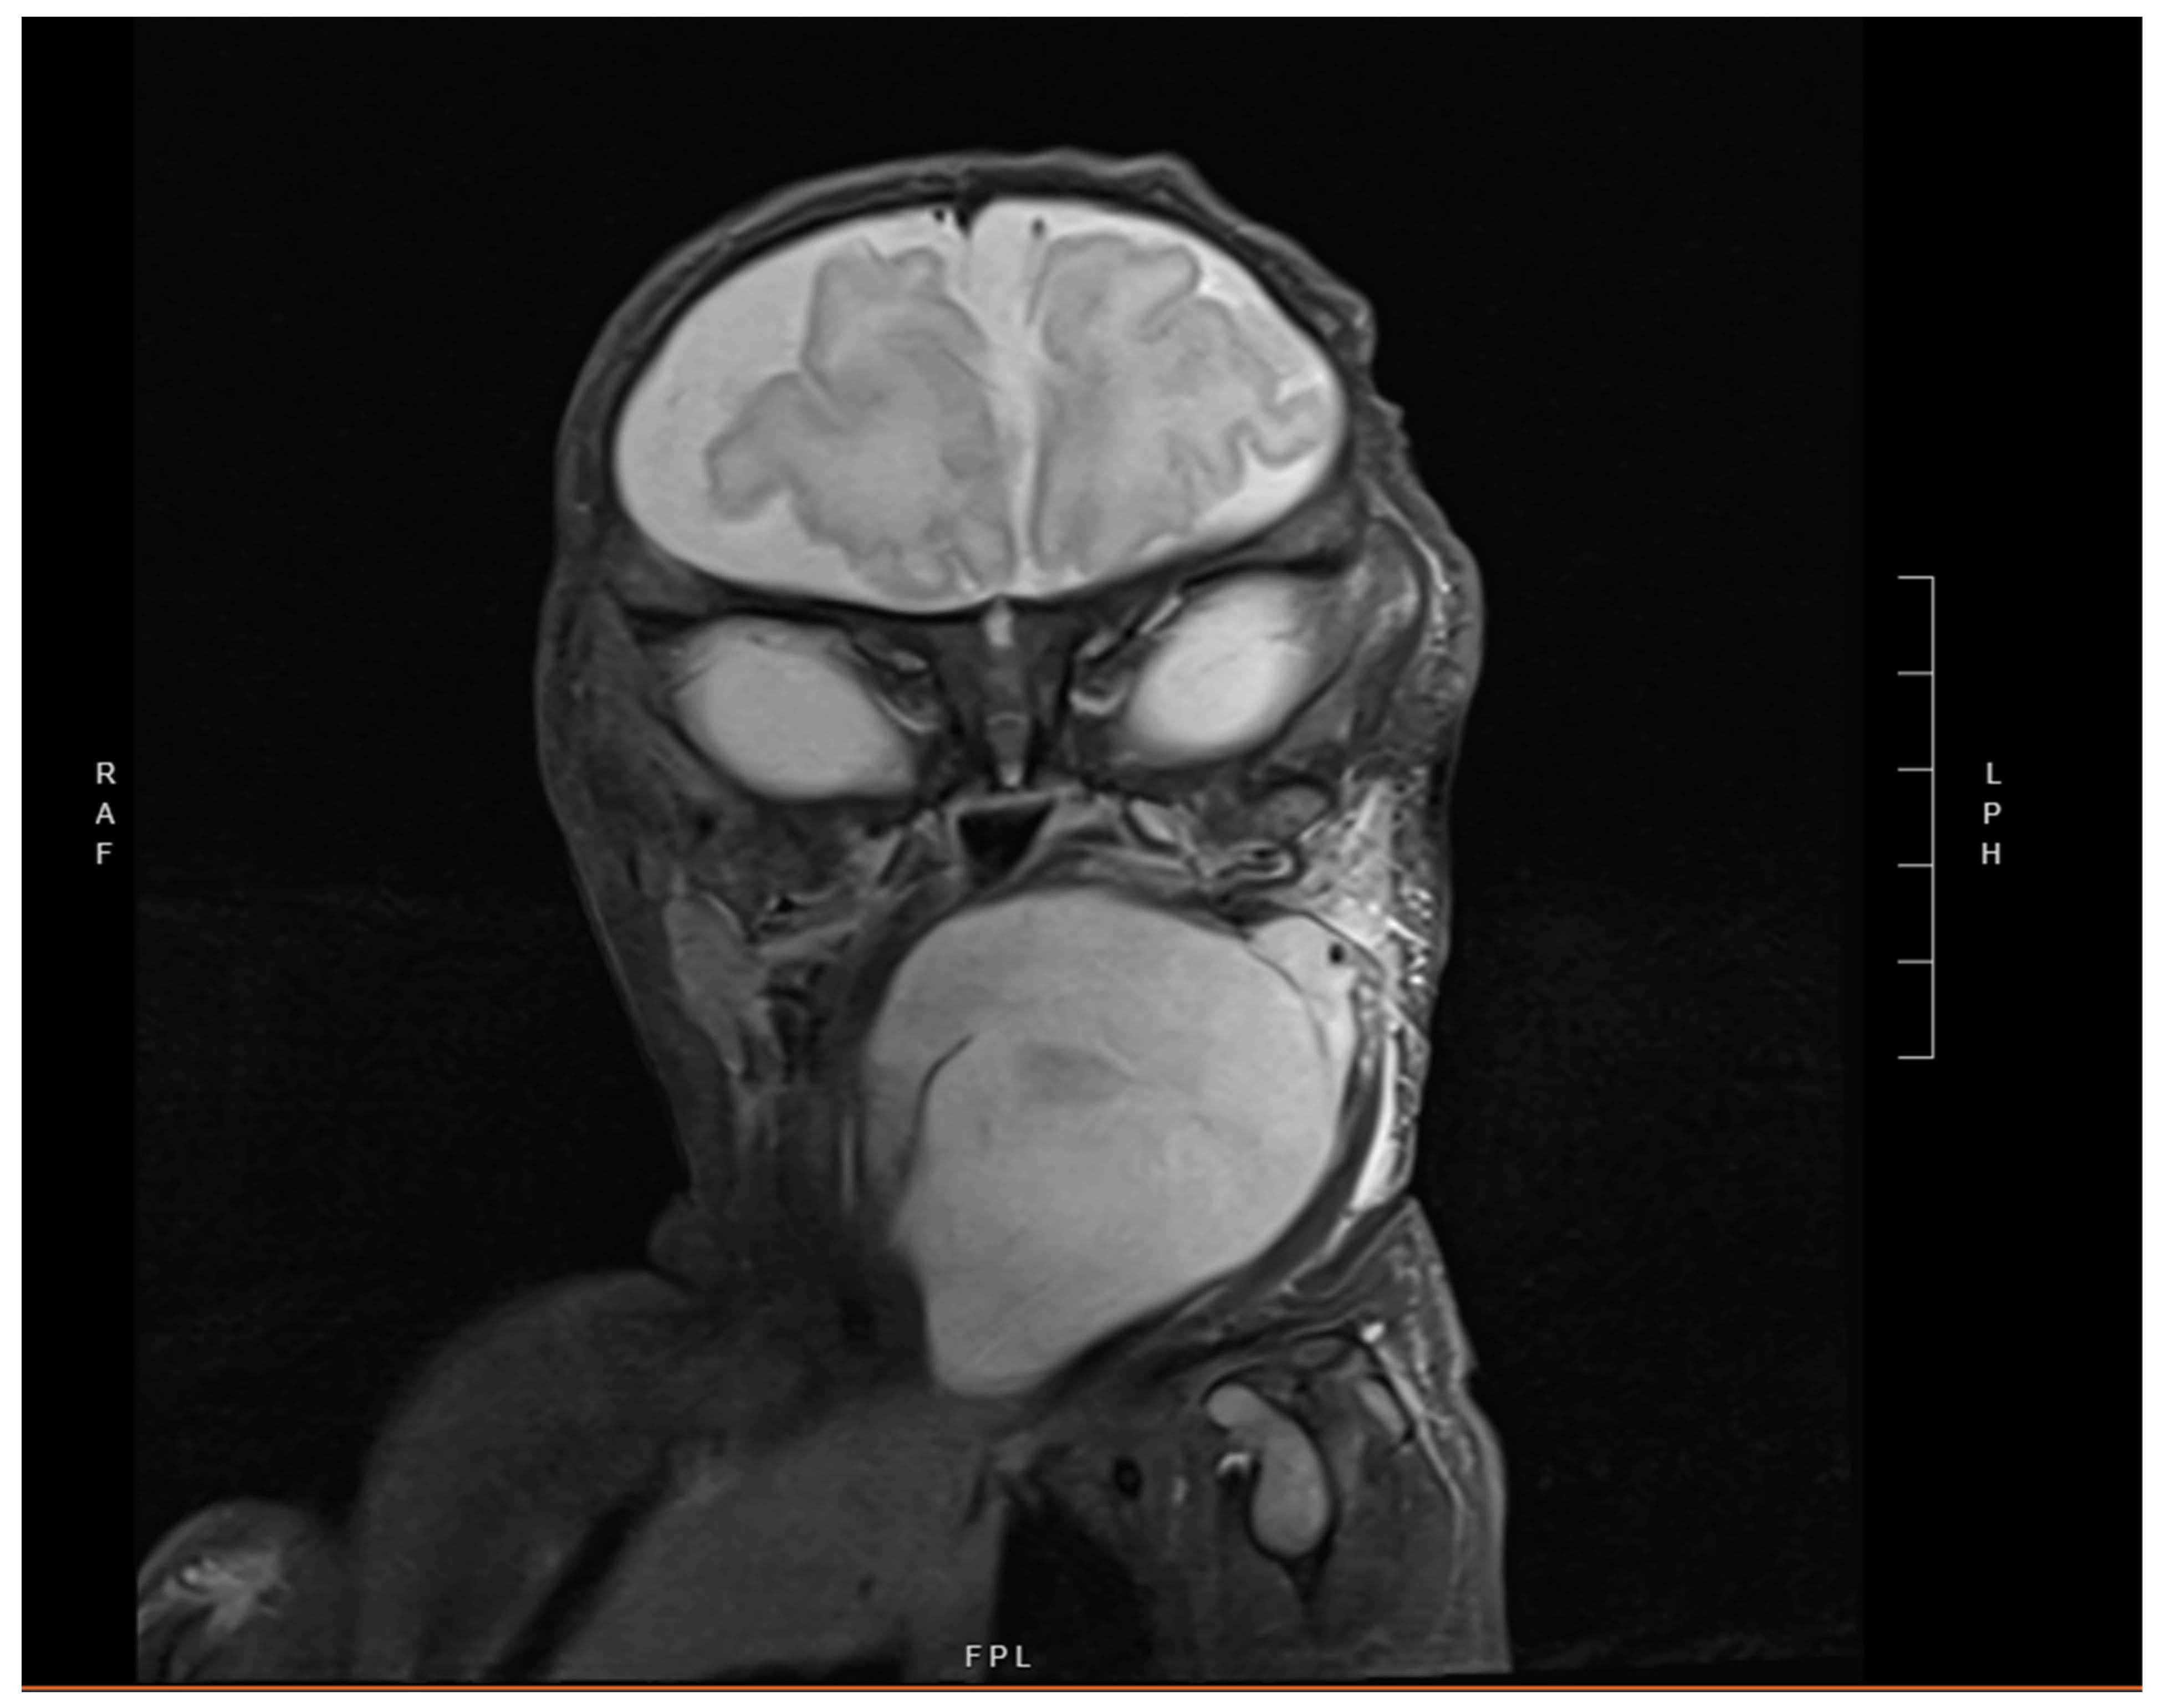

2. Case Presentation